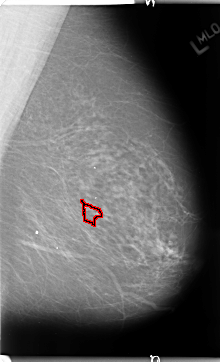

B_3126_1.LEFT_MLO

LEFT_MLO LINES 4696 PIXELS_PER_LINE 2856 BITS_PER_PIXEL 12 RESOLUTION 50 OVERLAY

FILE: B_3126_1.LEFT_MLO.OVERLAY

TOTAL_ABNORMALITIES 1

ABNORMALITY 1

LESION_TYPE CALCIFICATION TYPE PLEOMORPHIC DISTRIBUTION CLUSTERED

ASSESSMENT 4

SUBTLETY 3

PATHOLOGY BENIGN

TOTAL_OUTLINES 1

BOUNDARY